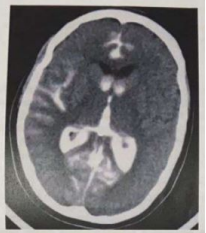

Mulher, 48 anos de idade, branca, chega no PS com história de cefaleia em trovoada, acompanhada de perda da consciência e monoparesia do membro superior esquerdo. AP: HAS não controlada e tabagismo. Ao exame: PA= 185 x 100 mmHg, P= 90 bpm (R), Temp.= 36,6º C, Glicose capilar= 110 mg %, Glasgow = 12 (A0 3 RV 3 RM 6); Aparelho Cardiovascular e respiratório sem anormalidades, assim como Abdome e membros sem alterações; Exame Neurológico: sonolenta/ confusa, monoparesia do membro superior esquerdo, com reflexos tendinosos vivos em ambos os lados e sinal de Babinski à esquerda. Pares cranianos: com pupilas isocóricas 3 mm/ fotorreagentes, reflexo córneo- palpebral (+) bilateral, sem alteração da motilidade ocular, reflexo óculo-cefálico (+); Cerebelo e sensibilidade: não colaborava, rigidez de nuca ++.